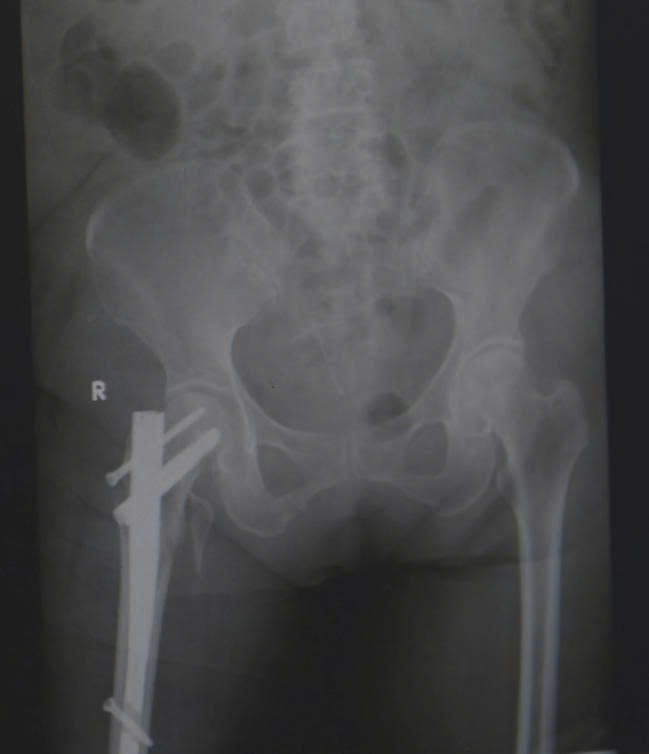

Sau khi đánh giá các nguy cơ và đạt được sự ổn định toàn thân, các bác sĩ khoa Chỉnh Hình Vi Phẫu tiến hành thực hiện ca phẫu thuật đóng đinh nội tủy đầu trên xương đùi – một kỹ thuật phổ biến trong điều trị gãy liên mấu chuyển. Phương pháp này giúp giữ vững cấu trúc xương, cho phép bệnh nhân xoay trở vận động, có thể ngồi dậy và tập vận động sớm.

Hình ảnh phim X-quang sau phẫu thuật đóng đinh nối tụy cho bệnh nhân gãy liên mấu chuyển xương đùi

Sau hai tuần phẫu thuật, bà T. có thể ngồi dậy, xoay trở cử động chân, cụ bà đã có thể ăn uống trở lại. Dù còn yếu, nhưng ánh mắt bà đã ánh lên niềm vui và sự nhẹ nhõm rất nhiều so với thời điểm nhập viện.